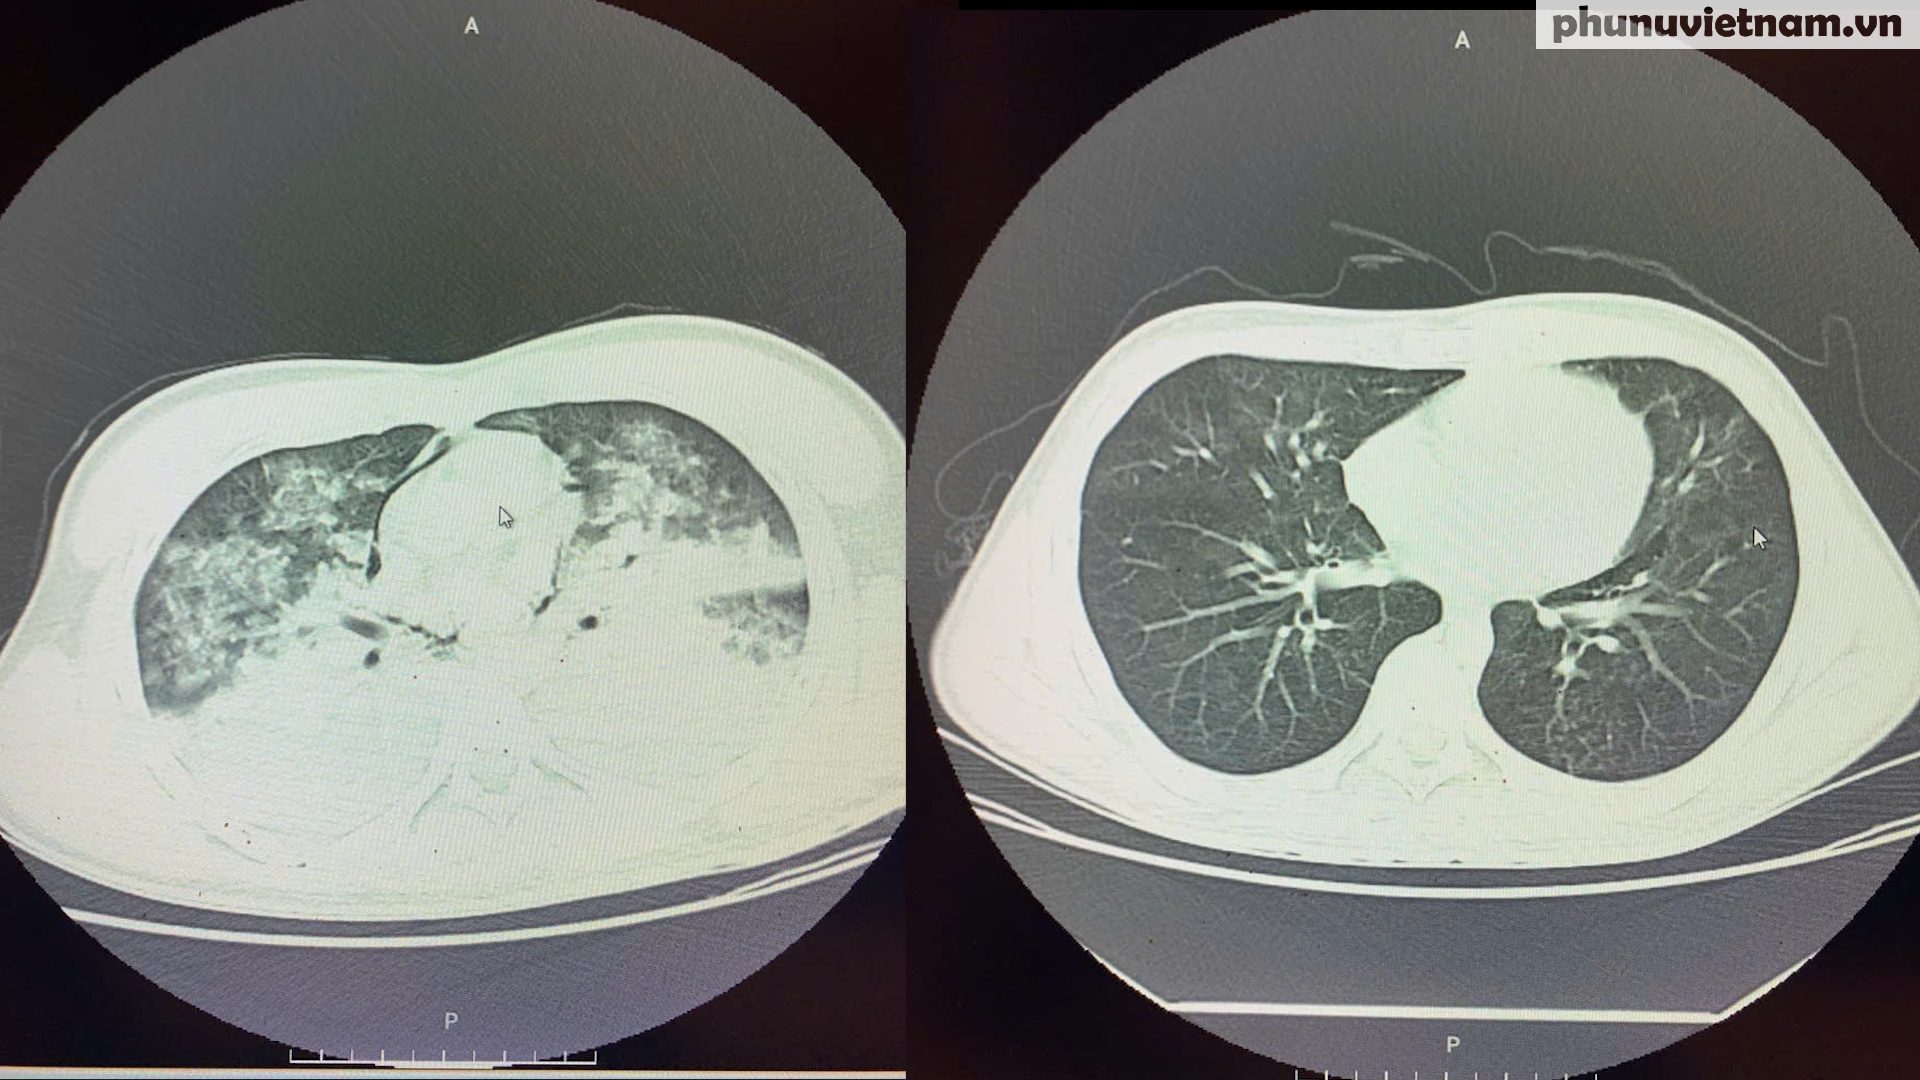

Tổn thương của phổi khi chụp cắt lớp vi tính (chụp CT) của bệnh nhân 19 tuổi bị đuối nước trước (trái) và sau (phải) khi điều trị

Khi được đưa tới Bệnh viện Thanh Nhàn, H. hôn mê sâu, phổi trắng xóa trên phim chụp, tim đập rời rạc. Các bác sĩ xác định đây là một trong những ca đuối nước nặng nhất mà họ từng gặp. Ê-kíp cấp cứu tiếp tục ép tim ngoài lồng ngực và triển khai hệ thống tim phổi nhân tạo (ECMO), biện pháp cuối cùng để giữ lại sự sống.

Suốt những ngày sau đó, chàng trai 19 tuổi nằm im trên giường bệnh, bao quanh là máy thở, dây truyền, thiết bị giám sát sinh tồn. Phổi bị viêm nặng do nước xâm nhập, tiêu hóa bị xuất huyết vì thuốc chống đông, có thời điểm cậu đi ngoài ra toàn máu. Các bác sĩ phải nội soi tại giường, truyền máu và tiểu cầu liên tục để cầm máu, đồng thời lọc máu, thở máy, thay ba quả ECMO liên tiếp.